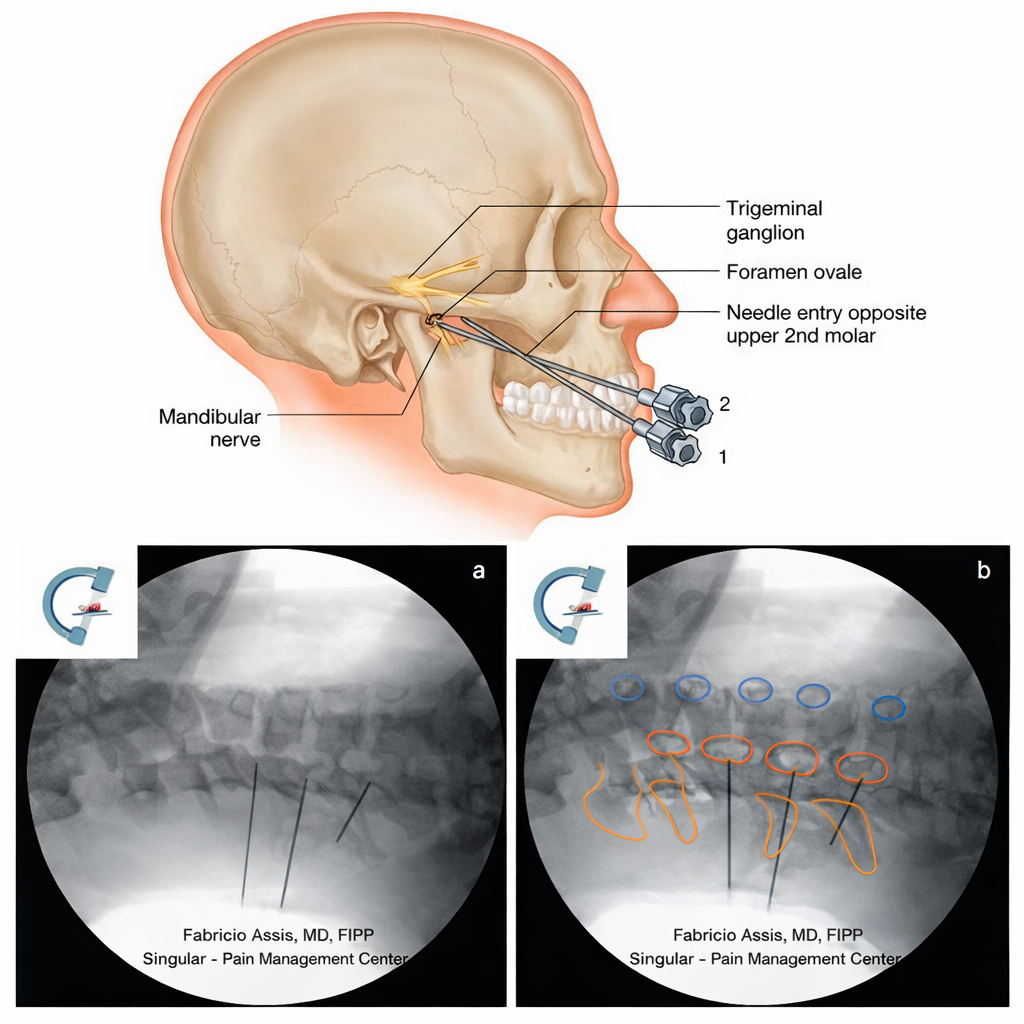

Trigeminal Nerve Blocks

- Used in trigeminal neuralgia and refractory facial-head pain treatment

- Provides rapid pain relief and diagnostic clarity

Cervical Medial Branch Blocks

- Fluoroscopy-guided injections targeting cervical facet joints